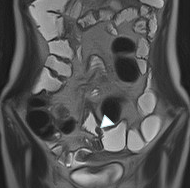

MRエンテログラフィー 2

腸管壁の肥厚と口側拡張を伴った狭窄を認める。